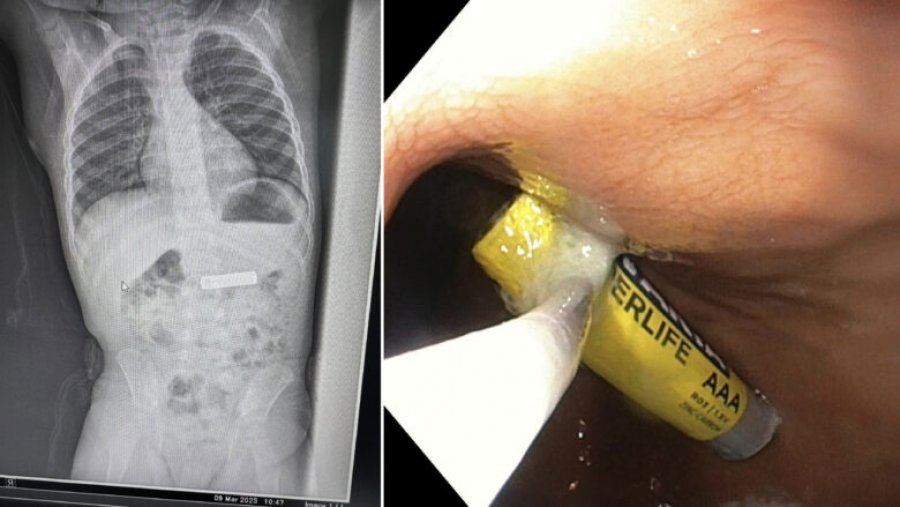

Gastroenterologu Besnik Elezi ia ka hequr nga barku baterinë e telekomandës një fëmije 2-vjeç.

“Largohet nga stomaku baterie e telekomandës te fëmija 2 vjet K.Sh”, ka shkruar Elezi.

Më poshtë mund t’i shihni fotografitë që i ka publikuar vet Elezi.